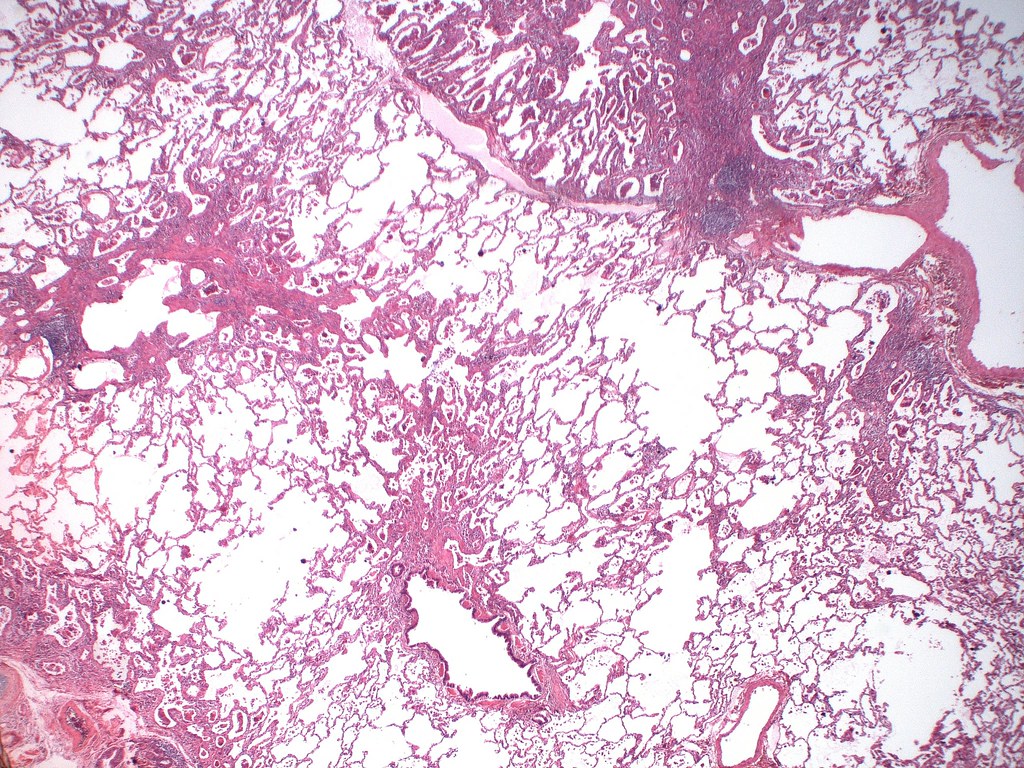

Hard metal lung disease/Giant cell interstitial pneumonia (GIP) Case Is Grinding Metal Bad For Your Lungs First, metallic titanium grindings were identified as an additional (in addition to tio 2 and. The amount of dust and the kinds of. Prolonged exposure to metal dust like steel, iron and cobalt can result in lung conditions such as siderosis and. Human lungs were designed for gas exchange. Certain work tasks, like heating or grinding metal, can increase lead. Is Grinding Metal Bad For Your Lungs.